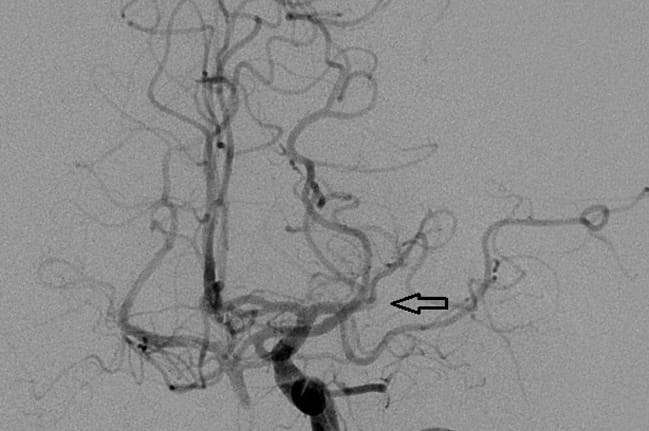

Patients were selected based on computed tomography (CT) and CT angiography (CTA). Inclusion criteria included large proximal intracranial vessel occlusion with small-core ischemic infarct in the anterior brain (i.e., patients with blockages in the large vessels of the head and neck who had a small amount of dead brain but a large area of at-risk brain). The procedure consisted of obtaining a cerebral angiogram, delivering a stentreiver to the blockage in the brain’s artery through the endovascular system, and suctioning out the thrombus (blood clot).